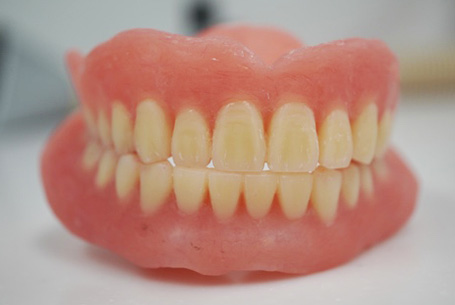

左:上の総入れ歯 / 右:下の総入れ歯

フルバランス:右側方運動時

真っすぐ噛んだ時

フルバランス:左側方運動時

噛み合わせをフルバランスにしたことで、食べ物をすり潰すことができ、野菜を食べられるようになりました。